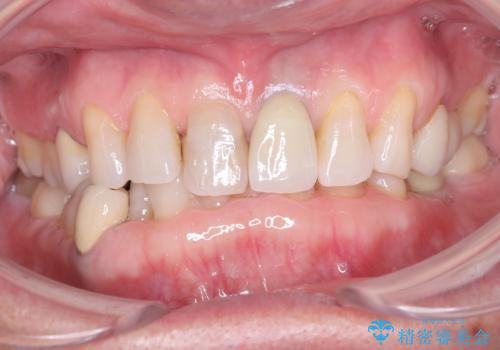

歯の変色を解消!根管治療とセラミック修復による審美的アプローチ

- 歯髄が死んで変色していた歯に対して、根管治療とオールセラミッククラウンでの修復を行いました。まず、根管治療で内部の感染を除去し、歯の強度を高めるためにファイバーコアを装着しました。その後、審美性と耐久性を考慮し、オールセラミッククラウンで覆うことで、自然な歯の色合いに近い美しい仕上がりを実現しました。

歯髄が死んだ歯は通常の健康な歯に比べて透過性が低く、特有の暗い色調を帯びる傾向にあります。変色は時間とともに進行し、薄い茶色や灰色、黄色がかった色合いになることが多いです。このような変色は、審美的な面で気になる場合が多く、オールセラミッククラウンなどでの修復が行われることも一般的です。